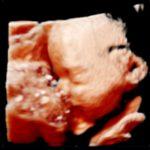

4D

Bewegende live 3D-beelden van je baby. Je ziet ‘live’ wat je baby doet: gapen, schoppen, draaien, duimzuigen… Met een 4D echo zie je beweging én kleur.